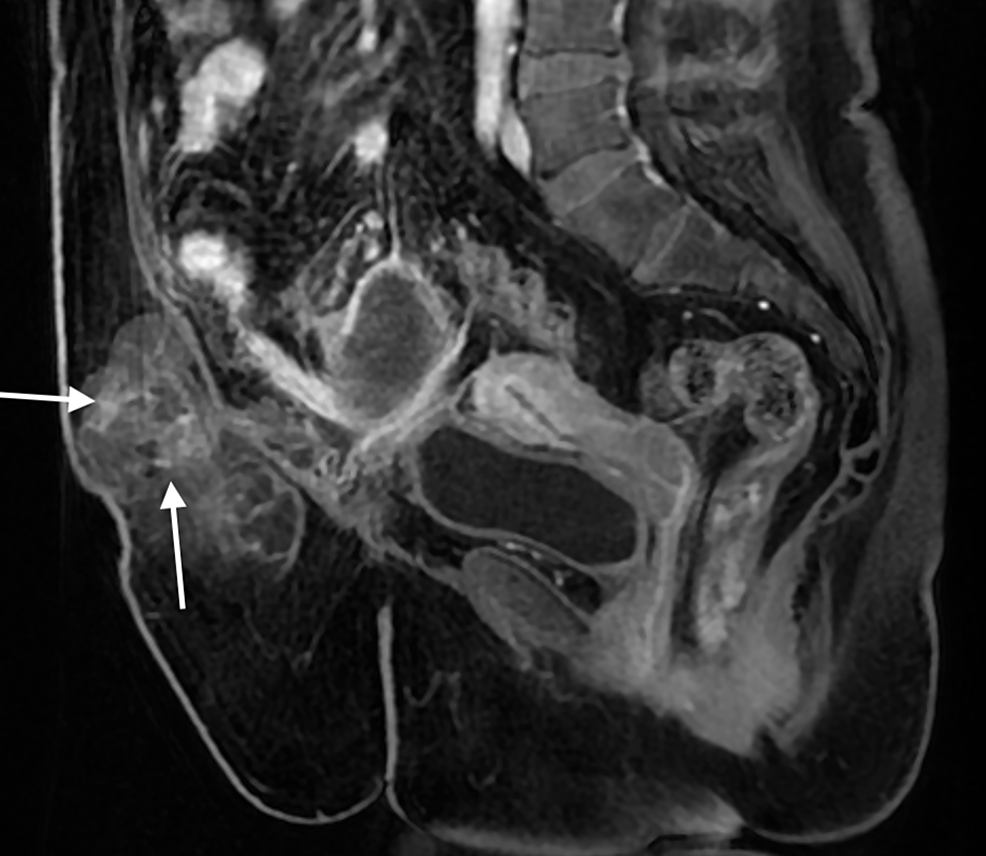

From www.cureus.com

Ruptured Appendiceal Mucocele Presenting as a Ventral Hernia A Case Ruptured Ventral Hernia Hernias can develop in several. Symptoms of a strangulated hernia include. In a strangulated ventral hernia, intestinal tissue gets tightly caught within an opening in your abdominal wall. A ventral hernia is the bulging of abdominal contents through the front of the abdominal wall. A hole or weakness in the. Umbilical and incisional hernias are specific types of. A ventral. Ruptured Ventral Hernia.

From www.researchgate.net

(PDF) Ruptured Appendiceal Mucocele Presenting as a Ventral Hernia A Ruptured Ventral Hernia A ventral (abdominal) hernia refers to any protrusion of intestine or other tissue through a weakness or gap in the abdominal wall. A ventral hernia, also known as an abdominal hernia, occurs when tissue protrudes through the abdomen wall due to a gap or weakness. Umbilical and incisional hernias are specific types of. Symptoms of a strangulated hernia include. A. Ruptured Ventral Hernia.

Cureus Ruptured Appendiceal Mucocele Presenting as a Ventral Hernia Ruptured Ventral Hernia Ventral hernias occur in the anterior abdominal wall and include primary ventral hernias (eg, epigastric, umbilical, spigelian,. Symptoms of a strangulated hernia include. A hole or weakness in the. Umbilical and incisional hernias are specific types of. Hernias can develop in several. A strangulated hernia is a hernia that is cutting off the blood supply to the intestines and tissues. Ruptured Ventral Hernia.